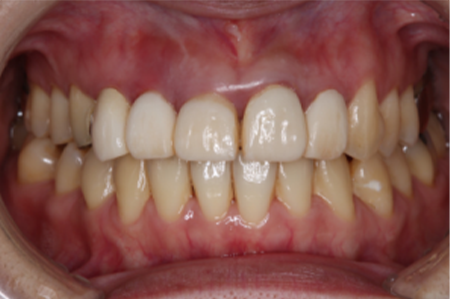

矯正治療と言っても、成人で虫歯の治療などが多数歯に渡って既に施されている場合、被せ物を変えていく必要があるのか、虫歯はないか、抜歯をする必要があるか、考えないといけないことがたくさんあります。

下の口腔内写真は初診時と矯正治療+補綴治療後のものになります。

一般的な矯正歯科ではできない審美治療など、矯正後のその先まで考えて治療計画を立案し治療を行っていくことが出来ます。

虫歯が大きかった右上の奥歯も残すことが出来ました。

連結してあった前歯の被せ物(歯茎まで黒くなっている)も矯正後にきれいに治療することが出来ています。

歯並びが悪いと見た目が悪いだけではなく歯磨きがしづらく、噛み合わせが悪いことで力のかかり方が不均一になってしまい歯に亀裂が入り虫歯になりやすくもなります。

当院ではトータルで口腔内を診ることに重きをおいて診療しています。

1本1本の歯にはそれぞれ役割があり、矯正治療を行うことでそれぞれの歯に適正な咬合力がいき渡るようにすることが出来、虫歯や歯周病になりづらい口腔内に、さらに審美的にもなります。

| 治療期間 | 2年 |

| 費用 | 矯正治療 88万円 調整料 5千円/毎回 補綴 ジルコニアクラウン 15万円×4本 |